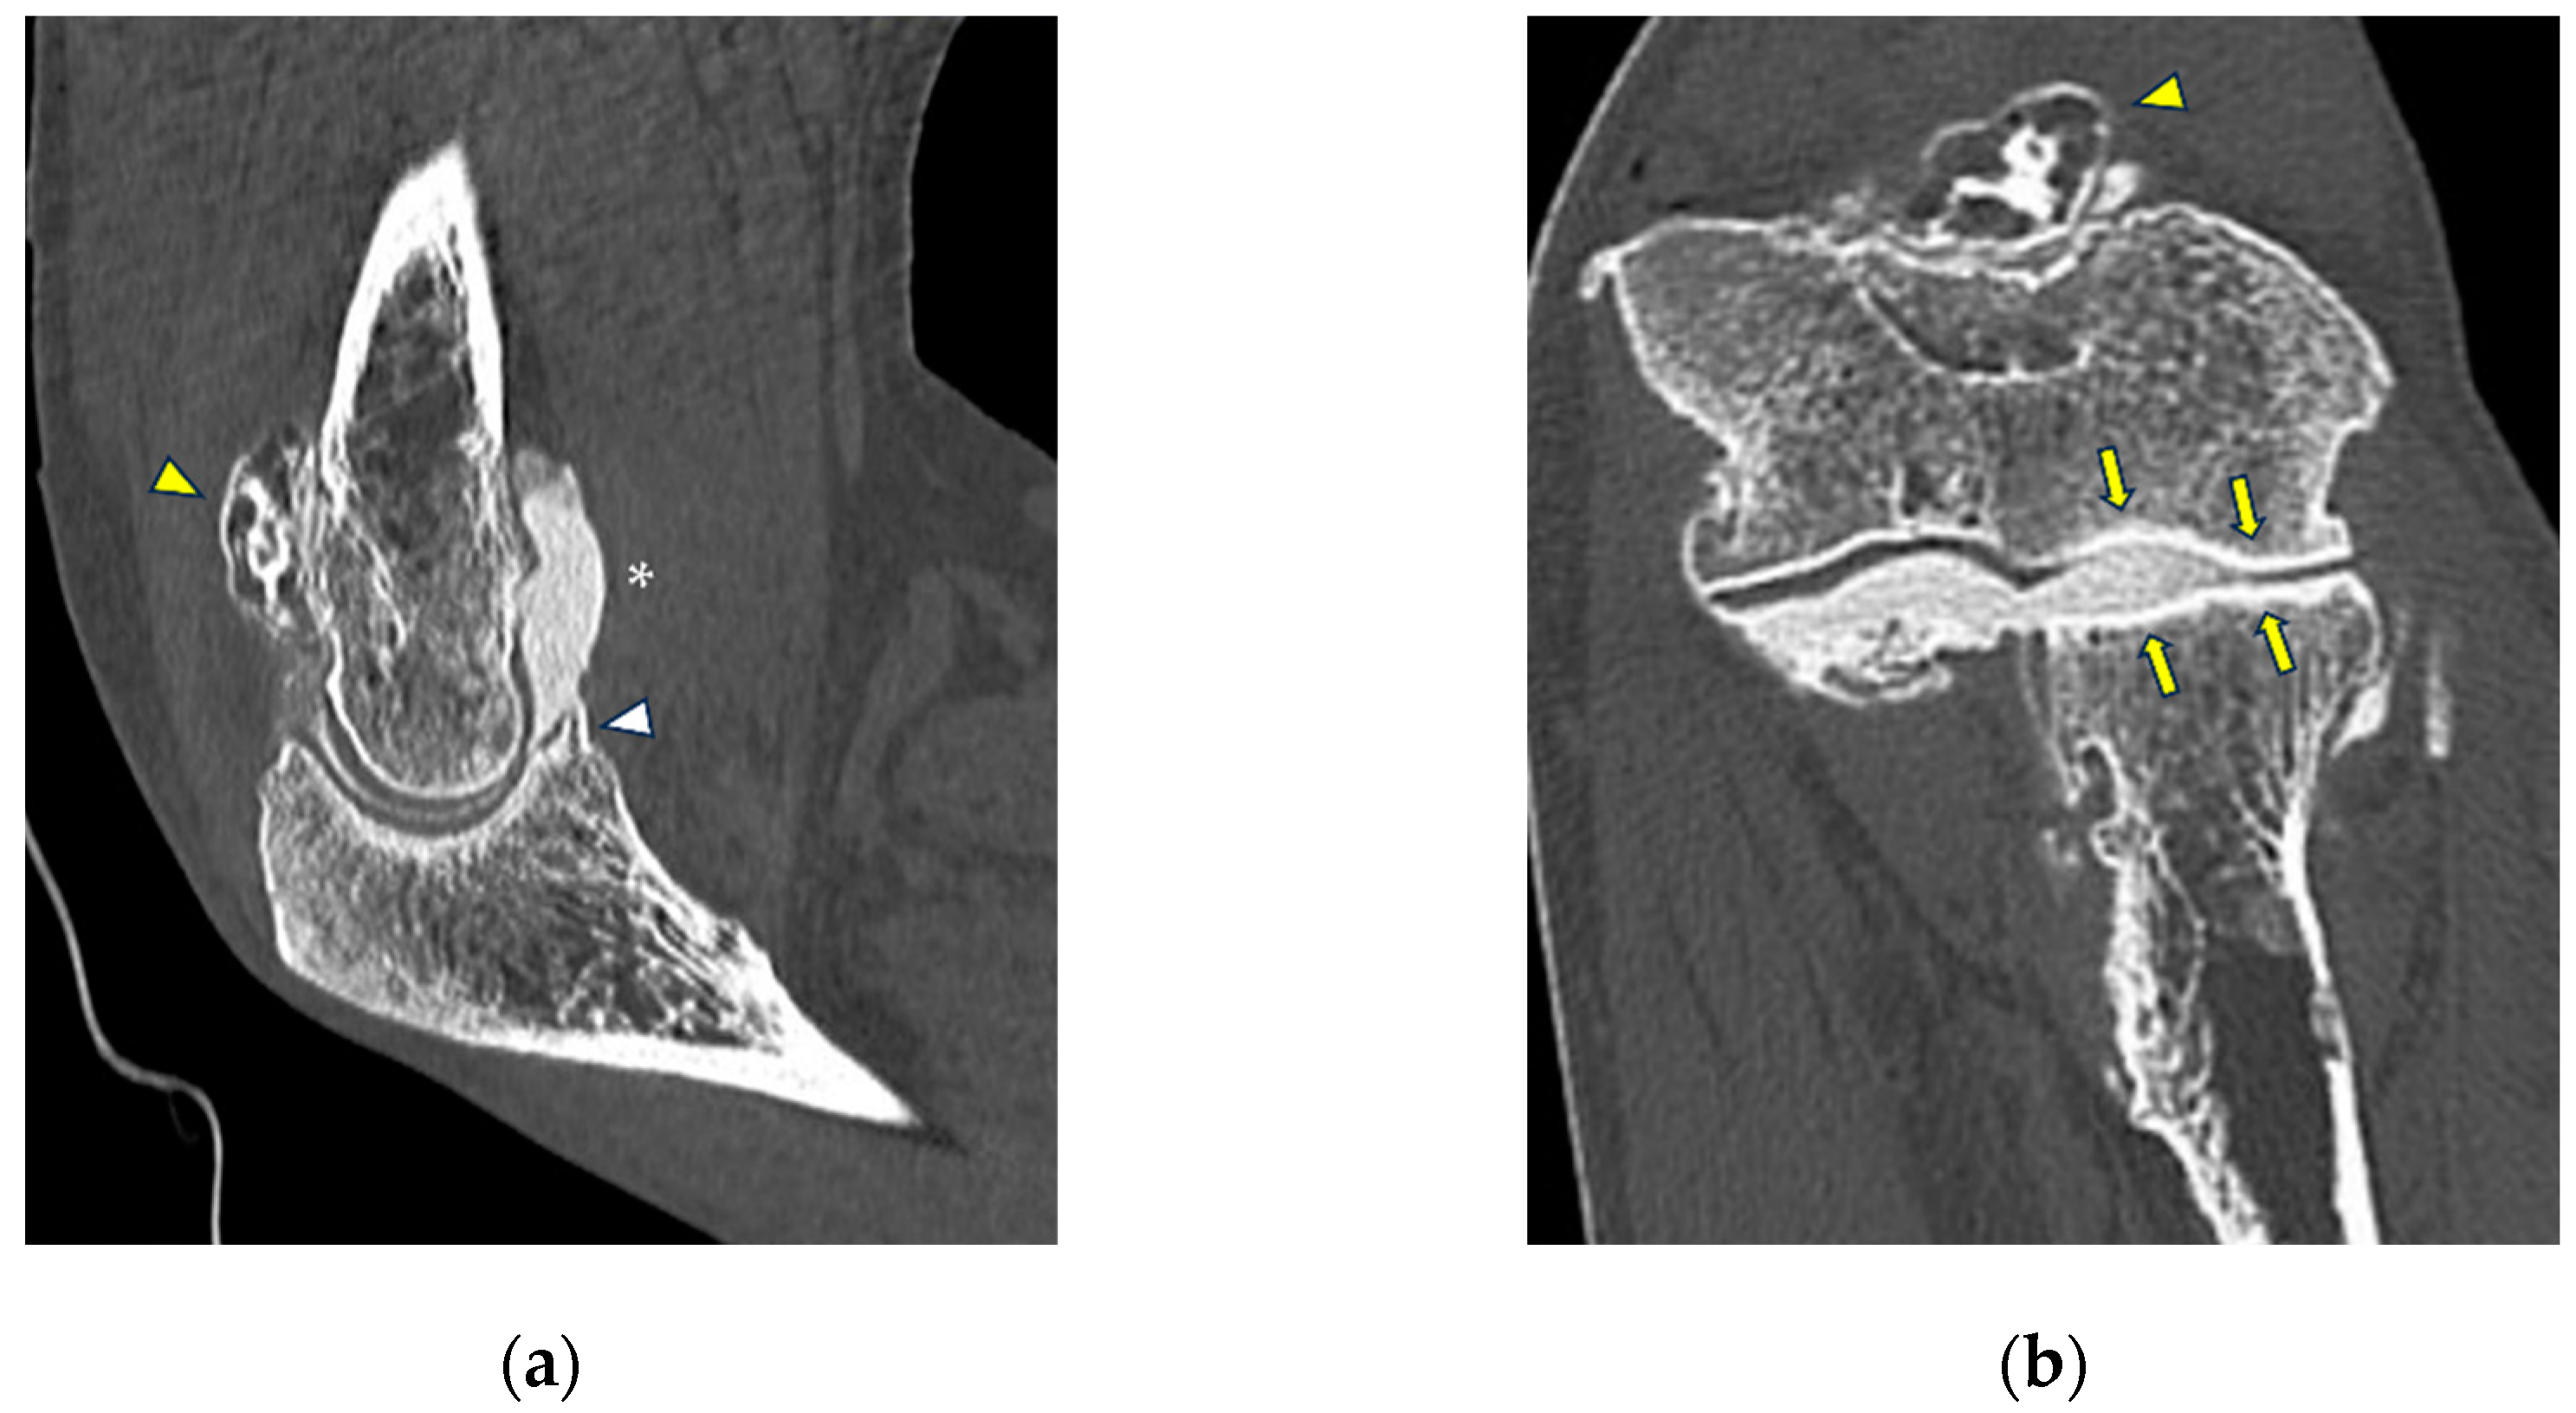

MCL injuries are typically caused by overuse [44]. Chronic injuries to the MCL may lead to medial elbow instability [50], which most often occurs in athletes who participate in overhead throwing sports such as baseball, javelin throwing, volleyball, golf, polo, and football. As stated previously, the main types of ligaments lesions that can be visualized at CT arthrography are represented by thickening or full-thickness or partial tears, which, however, in this setting are usually accompanied by other chronic local changes, such as the formation of osteophytes, presence of loose bodies or synovial thickening (Figure 6) [51]. The medial compartment may also present with posteromedial elbow impingement, which may in turn be associated with elbow instability due to MCL insufficiency [52]. Posteromedial elbow impingement is considered as a feature of valgus extension overload syndrome, presenting with pain, swelling, chondral injuries located into the posterior trochlea and the anterior and medial olecranon, postero-medial osteophytes, and loose bodies [52]. Imaging is essential for treatment decision-making, given that MCL tears would need surgical reconstruction after removal of osteophytes and loose bodies [53].

Figure 6.

CT-arthrography of a professional motocross rider with chronic elbow pain due to repeated microtraumatism. (a,b) Axial and sagittal images show pathological widening of the postero-lateral recess (yellow arrows); (b,c) sagittal and coronal images show articular asymmetry of the humero-radial joint (asterisks), diffuse cartilage fraying and a full-thickness chondral defect (grade IV) of the posterior aspect of the radial head dish (yellow arrowhead).

Overuse-related lateral elbow pain, often diagnosed as lateral epicondylitis, may be often associated with a condition of elbow instability termed symptomatic minor instability of the lateral elbow (SMILE), which has been shown to present with several intra-articular findings detectable at CT arthrography, such as radiocapitellar chondromalacia and pathological laxity of the annular ligament (Figure 7) [54]. Extreme cases of concomitant LCL and common extensor tendon full-thickness rupture can also sometimes be seen as sequelae of repeated corticosteroid injections performed without US guidance for the treatment of lateral epicondylitis [55], with extravasation of intra-articular contrast agent in peritendinous soft tissues (Figure 8).

Figure 7.

CT arthrography of a patient with overuse-related lateral elbow pain. (a) Sagittal image shows pathological widening of the radio-humeral and radio-annular recesses (white arrowheads) due to ligamentous laxity—in particular, the annular ligament (white arrow) is displaced distally to the proximal half of the radial head side, which also shows anterior cartilage thinning and synovial thickening (asterisk); (b) the corresponding coronal reformat may aid in precise localization of the proximal extremity of the annular ligament, which can be visualized as a hypodense band anterior to the radial head (white arrows); in this instance, it shows marked distal displacement.

Figure 8.

CT arthrography of a patient with lateral epicondylitis subjected to multiple corticosteroid injections. (a,b) Coronal and axial images show extravasation of intra-articular contrast into lateral periarticular soft tissues through a large full-thickness tear of both the radial collateral ligament and the proximal common extensor tendon (white arrowheads). Diffuse thinning of radial head dish cartilage is also displayed (white arrows); (c) sagittal image also shows distal displacement of the annular ligament (yellow arrowhead) and cartilage fraying of the radial head side (yellow arrow).